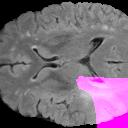

Weakly Supervised Semantic Segmentation (WSSS) relying only on image-level supervision is a promising approach to deal with the need for Segmentation networks, especially for generating a large number of pixel-wise masks in a given dataset. However, most state-of-the-art image-level WSSS techniques lack an understanding of the geometric features embedded in the images since the network cannot derive any object boundary information from just image-level labels. We define a boundary here as the line separating an object and its background, or two different objects. To address this drawback, we are proposing our novel ReFit framework, which deploys state-of-the-art class activation maps combined with various post-processing techniques in order to achieve fine-grained higher-accuracy segmentation masks. To achieve this, we investigate a state-of-the-art unsupervised segmentation network that can be used to construct a boundary map, which enables ReFit to predict object locations with sharper boundaries. By applying our method to WSSS predictions, we achieved up to 10% improvement over the current state-of-the-art WSSS methods for medical imaging. The framework is open-source, to ensure that our results are reproducible, and accessible online at https://github.com/bharathprabakaran/ReFit.